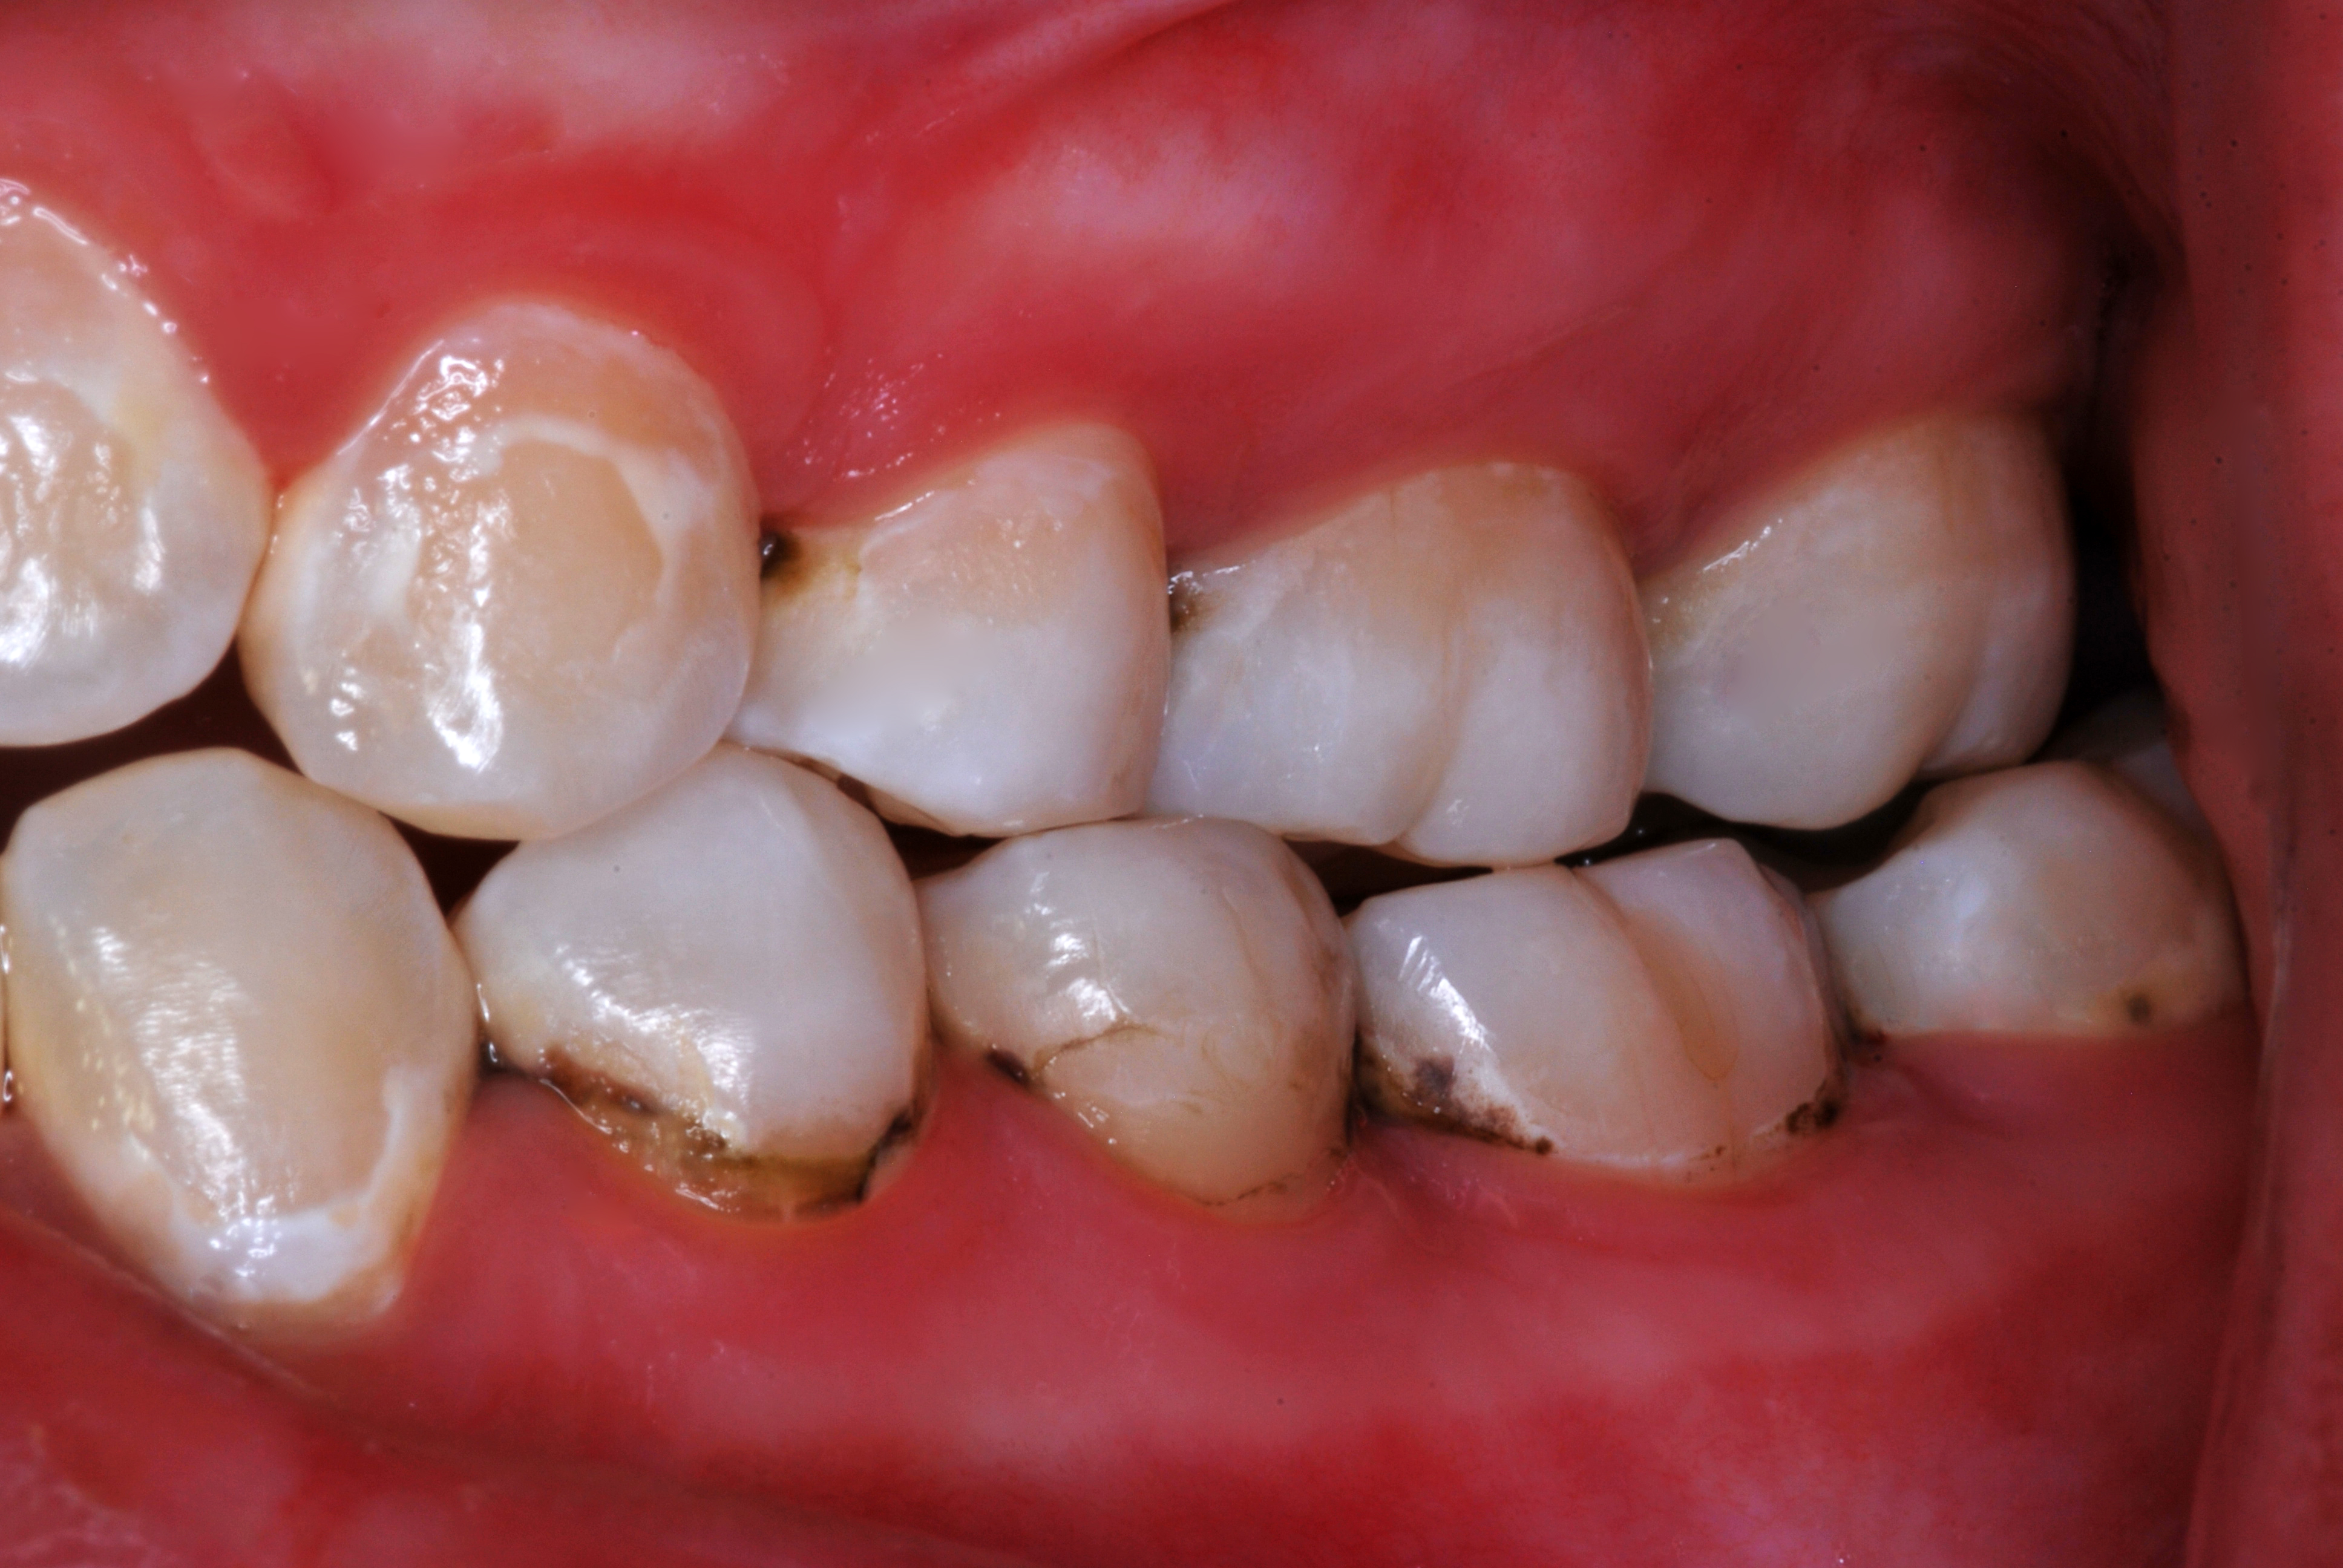

(23.) Teenage patient who had SDF applications every four months for 16 months. Flossing compliance was poor, and several teeth will require restorative care.

Figure 23